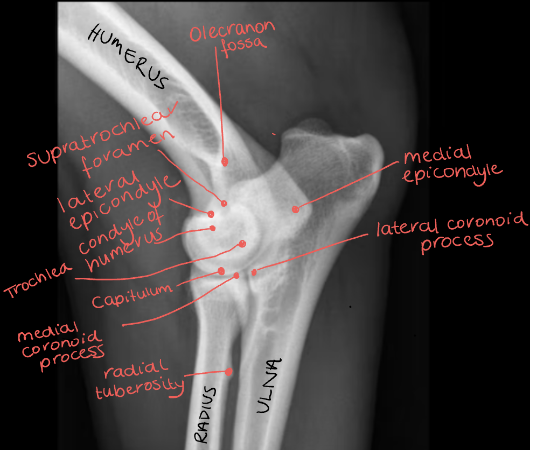

Q

Label the image